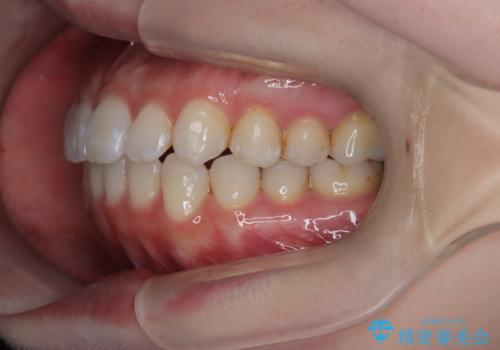

【インビザライン】がたつきをなおしたい

- 上下の前歯の凸凹が気になり、来院されました。

インビザラインで綺麗に仕上がり、満足していただきました。